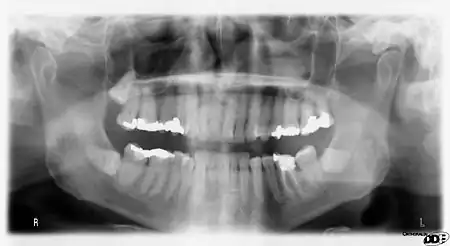

Panoramic films

Panoramic films are extraoral films, in which the film is exposed while outside the patient's mouth, and they were developed by the United States Army as a quick way to get an overall view of a soldier's oral health. Exposing eighteen films per soldier was very time consuming, and it was felt that a single panoramic film could speed up the process of examining and assessing the dental health of the soldiers; as soldiers with toothache were incapacitated from duty. It was later discovered that while panoramic films can prove very useful in detecting and localizing mandibular fractures and other pathologic entities of the mandible, they were not very good at assessing periodontal bone loss or tooth decay.[21]